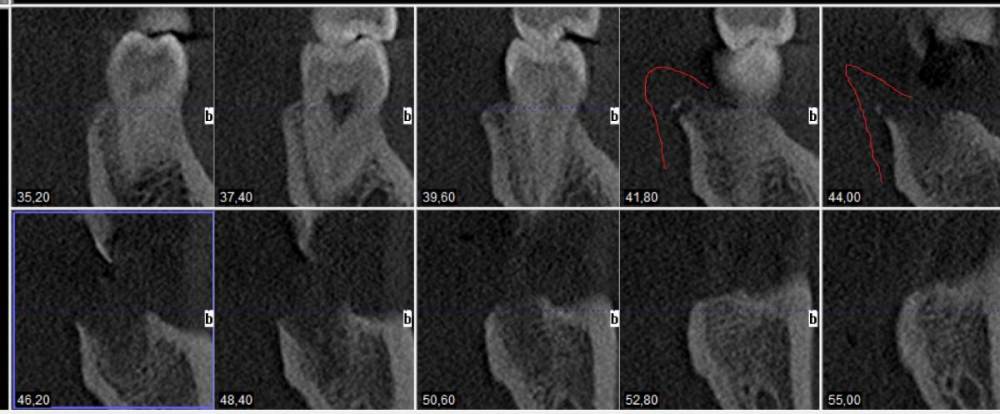

ЕвгенийЗ Опубликовано 24 июня, 2021 Автор Поделиться Опубликовано 24 июня, 2021 И если немного выше поднять плоскость, то как раз виден этот край альвеоллы(или как правильно?). Но он вроде как отколат что ли? Не могли бы взглянуть пожалуйста. Там где стрелочка, походу этот край и вылез. И еще плоскость по зубному ряду Ссылка на комментарий

ЕвгенийЗ Опубликовано 24 июня, 2021 Автор Поделиться Опубликовано 24 июня, 2021 Дополнение к последнему фото. Это вот эта плоскость Ссылка на комментарий

АнтонТЛТ Опубликовано 24 июня, 2021 Поделиться Опубликовано 24 июня, 2021 Да, это этот край альвеолы 1 Ссылка на комментарий